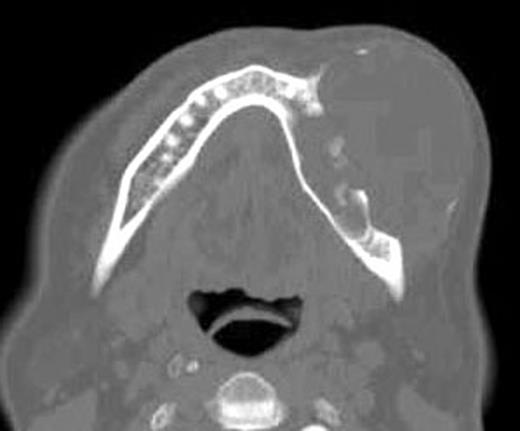

Preoperative axial CT view shows the lesion with destruction the medullar and buccal cortical portions of the left mandible.

The clinical, radiolological and tomography signs (Fig. 3) evoke the hypothesis of a KCOT or ameloblastoma. An incisional biopsy and cytological smears were done and the results showed thin epithelial layer, composed of from 8 to 10 cell. The basal layer shows palisade organized cells with a uniform nucleus. In the direction of the cyst lumen, there is parakeratosis with a focal zone created of orthokeratins. The palisading appearance of the basal cells was evident and confirms the diagnosis of KCOT.